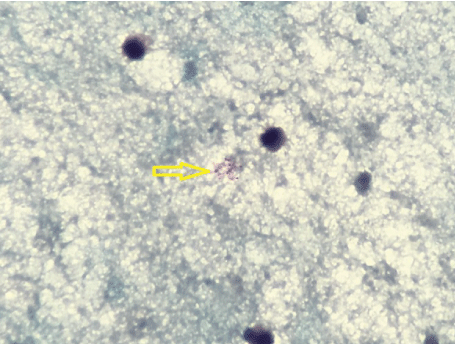

We ordered sputum Acid Fast Bacillus (AFB) smears, urine Histoplasma antigen which is endemic in this region and placed her in respiratory isolation. Chest X-ray showed minimal infiltrate in the right peri-hilar region. The left lung field is clear. No pneumothorax or pleural effusion. Trachea is midline. The cardiac silhouette is within normal limits. We consulted hematology and oncology as malignancy is one of the differentials in this case. Contrast Tomography (CT) scan of the neck with intravenous contrast revealed irregular, ill-defined peripherally enhancing collection in the right posterolateral neck with increasing liquefaction and mass effect, and Necrotic, peripherally enhancing bilateral cervical lymph nodes (Figure 2). Otolaryngology team performed Fine Needle Aspiration Cytology (FNAC) of the lesion which revealed abundant acute inflammation on pathology, and AFB smear was positive (Figure 3). Aspirate cultures were inoculated to Lowenstein Jensen-Gruft and Middlebrook 7H11 slants, incubated for 42 days at 35-37 degree Celsius at 6-8% CO2. Cultures were positive for Mycobacterium Tuberculosis Complex after 14 days. Identification was confirmed by the Hologics GenProbe Accuprobe, RNA/DNA hybridization and susceptibility test was performed by Quest Diagnostics Infectious Disease by Agar methodology for Ethambutol, Isoniazid, Rifampin, and Streptomycin and broth method used for Pyrazinamide (Table 1).

Figure 3: Positive for few Acid Fast Bacilli from the aspirate of the right cervical lymph node mass. View Figure 3